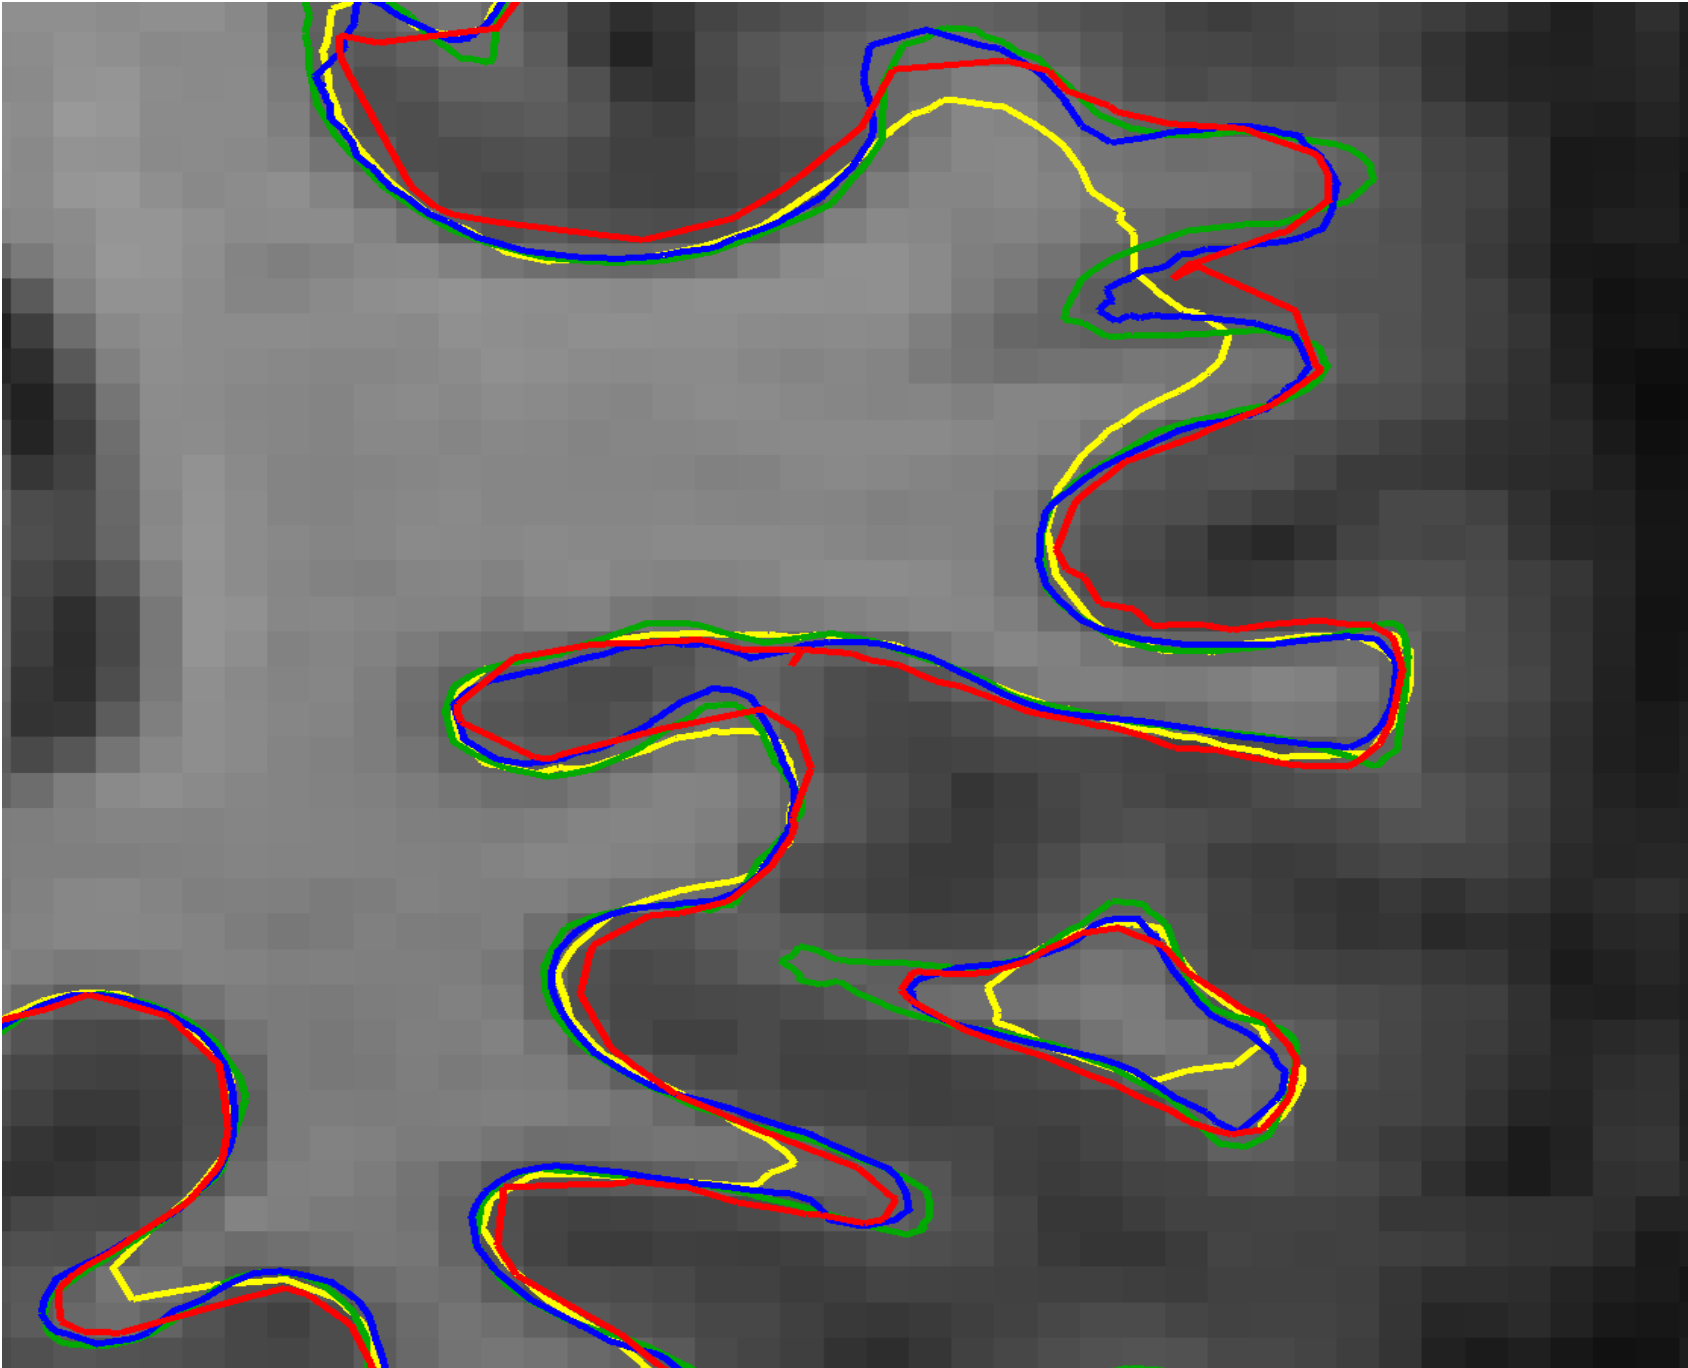

Figure 5: Cortical surface reconstructions: SimCortex (yellow), CFPP (blue), V2C (red), and ground truth (green). (a) Coronal view with MRI overlay. (b) RH pial surfaces detail. (c) LH white matter surfaces detail.

Figure 6: Coronal views comparing inter-hemispheric intersections of pial surfaces: SimCortex (yellow) versus CFPP (right hemisphere: dark blue, left hemisphere: light blue). (a) Overview, (b–c) Intersection region details.

3.3.3 Visual Analysis

Figure 5 compares cortical surface reconstructions by SimCortex, CFPP, and V2C against ground truth surfaces. SimCortex captures deeper sulci in some regions but occasionally produces smoother surfaces lacking detailed curvature; CFPP is generally accurate; V2C is less precise. For the white matter surfaces, CFPP and V2C closely match ground truth sulcal depth, whereas SimCortex shows shallower sulci, indicating a model limitation. Fig. 6 compares SimCortex and CFPP regarding hemispheric intersections. SimCortex (yellow) effectively avoids intersections, while CFPP shows collisions between right (dark blue) and left (light blue) hemispheres. V2C demonstrates hemispheric intersections similar to CFPP.